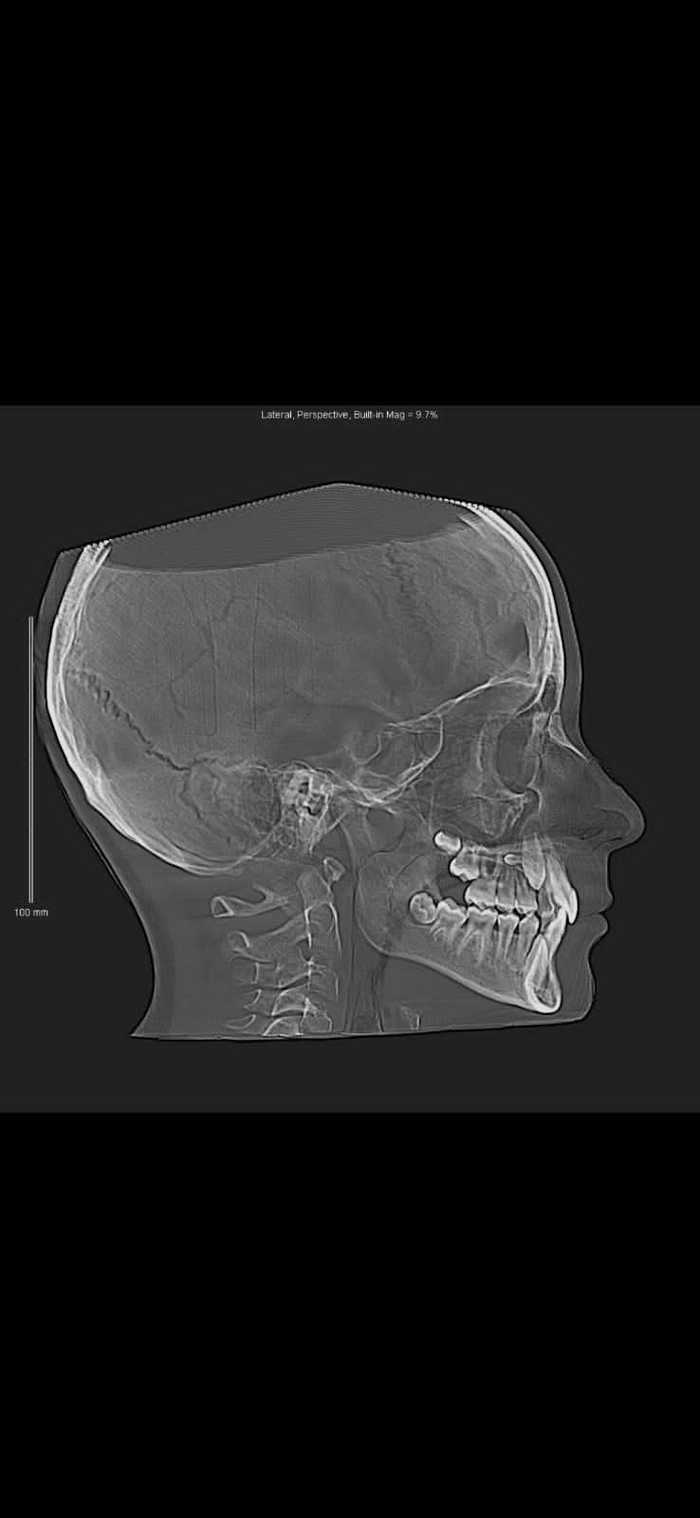

Поэтому одним из вариантов лечения проблемы с десневыми карманами в зависимости от стадии болезни может быть такая процедура, как лоскутная операция, именно в случаях, когда боевые действия в вашей полости рта перешли уже на костную ткань в районе корня зуба.

Стоматолог вскрывает десневой карман на глубину поражения и производит очистку отложений, а затем делает подсадку ткани, стимулирующей рост костной ткани на месте пораженного участка. Уже после этого десну зашивают в правильном положении относительно зуба.

Он уже в процессе лечения увидит, что происходит у вас на зубных корнях и в тканях около зуба, чтобы сделать наиболее эффективные манипуляции для решения проблемы.